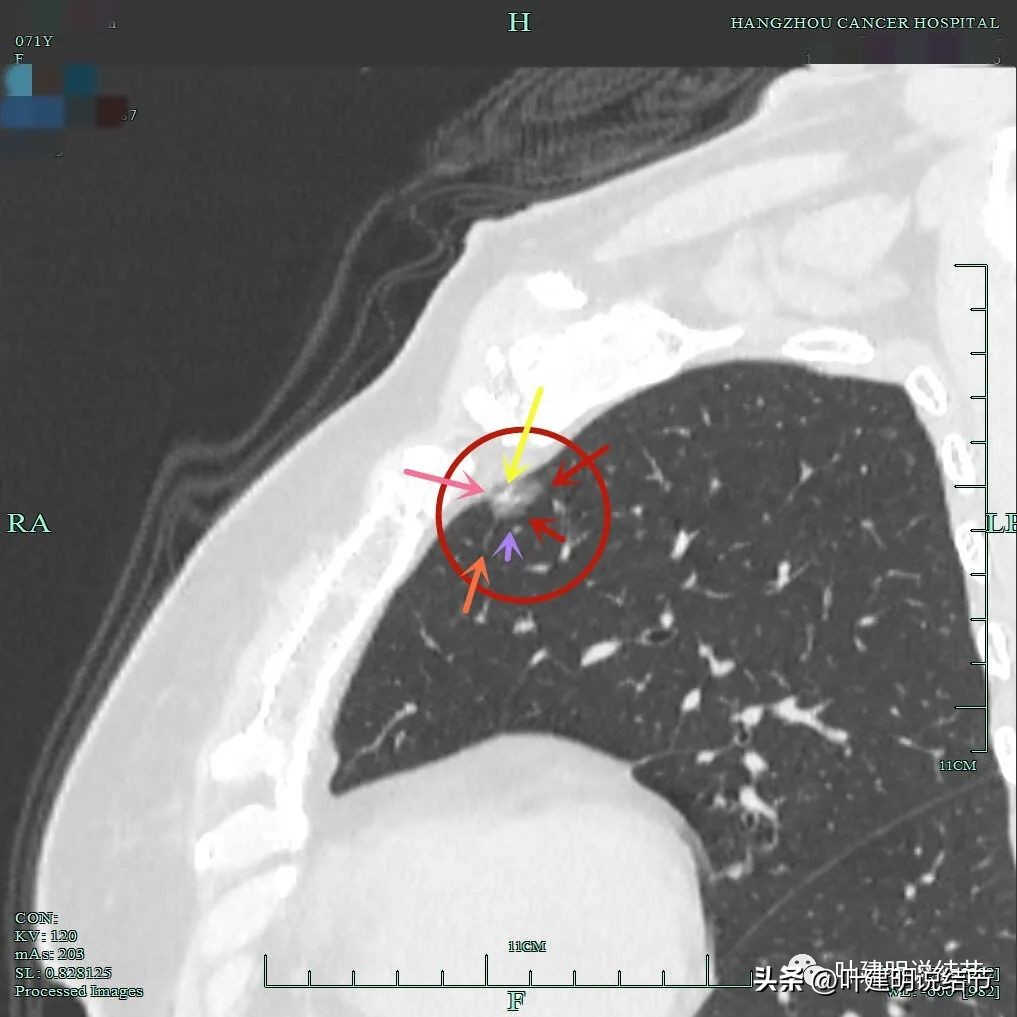

靶扫描显示主病灶混合磨玻璃密度,边缘实性成分(粉色箭头);瘤肺边界清(红色箭头);部分边缘似有毛刺(紫色箭头)。

灶内实性成分(粉色箭头)以及微血管进入(桔色箭头);整体密度不均,轮廓与瘤肺边界清(红色箭头)。

微血管征、毛刺征、混合磨玻璃密度、胸膜间隙征(黄色箭头)。